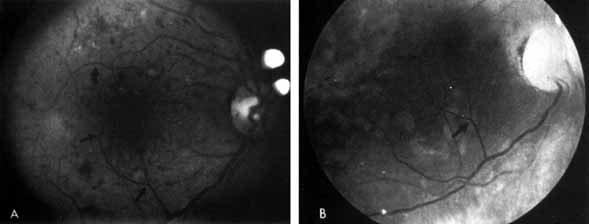

Fig. 3 A. Diabetic retinopathy with multiple microaneurysms, dot hemorrhages, and early neovascularization of the optic disc (NVD). A small blot hemorrhage is seen inferiorly. B. Continued. Midphase of the fluorescein angiogram. Patent microaneurysms are seen as hyperfluorescent dots. Note that most microaneurysms cannot be seen ophthalmoscopically. There is some enlargement of the foveal avascular zone because of some occluded capillaries. Temporally there is a larger zone of capillary nonperfusion. The NVD is beginning to leak. C. Late phase of the fluorescein angiogram showing diffuse leakage of fluorescein into the macula.

It is often difficult to distinguish a small dot hemorrhage from a microaneurysm by ophthalmoscopy alone. On fluorescein angiography patent microaneurysms will fill with dye quickly and then leak,5 unlike a small dot hemorrhage that will block fluorescence (see Fig. 3). However, angiography cannot distinguish a hemorrhage from a microaneurysm filled with clotted blood. Because fluorescein passes easily though them, we usually see many more microaneurysms on fluorescein angiography than are apparent on examination.6

When the wall of a capillary or microaneurysm is thin, it may rupture, giving rise to an intraretinal hemorrhage. If the hemorrhage is deep (i.e., in the inner nuclear layer or outer plexiform layer), it usually has a round or oval shape (“dot or blot”) (see Fig. 3). Superficial (nerve fiber layer) hemorrhages, on the other hand, become flame- or splinter-shaped indistinguishable from that seen in hypertensive retinopathy. Although people with diabetes with normal blood pressure may have multiple splinter hemorrhages, they should nevertheless have their blood pressure checked because a frequent complication of diabetes is systemic hypertension.